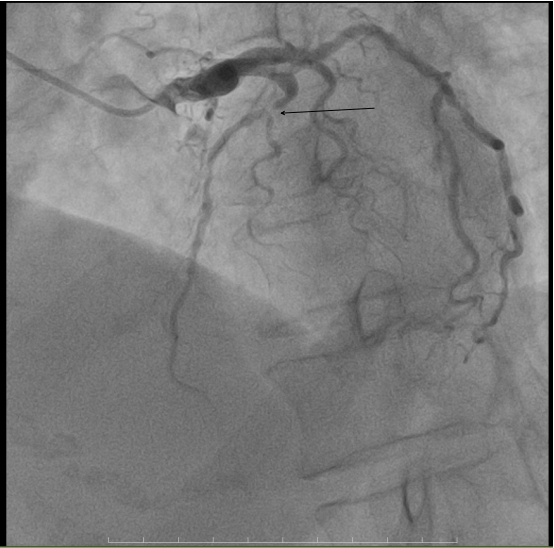

▲术前冠脉造影

术前心电图呈现出与该病症相符的典型特征。入院后急诊冠脉造影显示,前降支近中段于第二对角支发出前后节段性病变,最重狭窄程度高达98%,情况危急万分。但我院介入团队凭借丰富的临床经验和娴熟的操作技术,顺利引导导丝通过病变部位,随即开展球囊扩张操作,而后精准植入一枚2.75*18mm支架。术后造影结果令人满意,患者的心肌供血状况得到显著改善,为后续康复奠定了坚实基础。